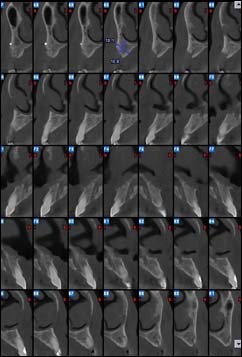

EXAMENS TOMOGRAPHIES VOLUMIQUES TYPE SCANNER OU CÔNE BEAM :

Dernière technologie à notre disposition, cette technique permet de voir en 3 dimensions des images de votre bouche et de mettre en évidence des pathologies ou des anomalies que les autres techniques ne permettent pas d’objectiver.

Coupe axiale

Reconstruction panoramique

Reconstruction coronale